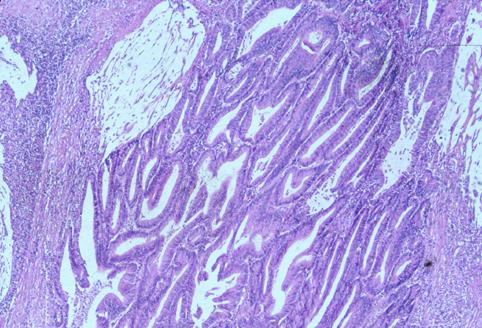

疾病(病理主体)的分类恶性上皮性肿瘤/腺癌

部位(按器官分)大肠/阑尾

检查方法病理切片(微观)

肿瘤的肉眼分类2型(溃疡局限型)/

肿瘤最大直径25~29

肿瘤的深度s(a)